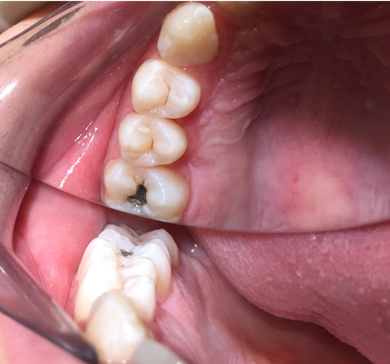

Fig 15. Bitewing of an 11-year-old boy.

Figure 15

Figure 15 shows bitewings of an 11-year-old boy with high caries risk and history of proximal "kissing lesions" on his primary molars in all four quadrants. He then presented with incipient lesions in his permanent teeth. After resin infiltration (Figure 16), results have been stable for 2 years.